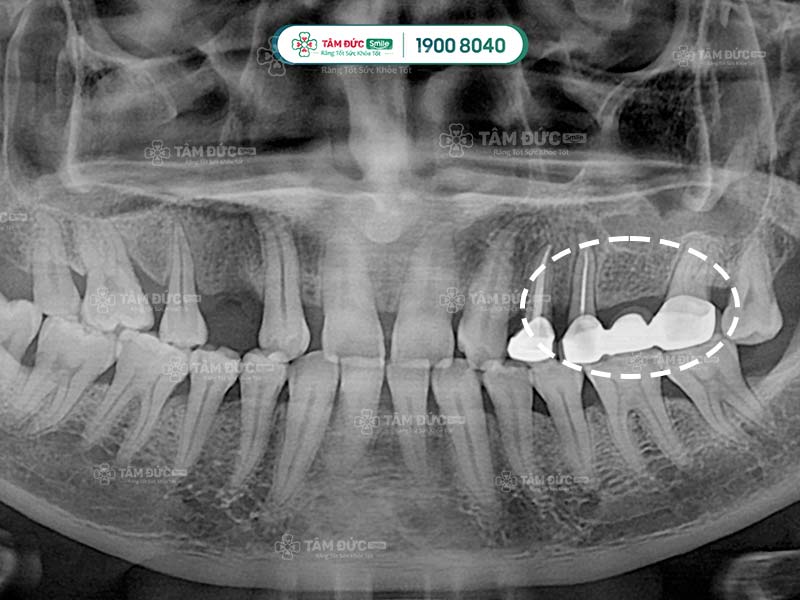

Cầu răng sứ qua phim X-Quang